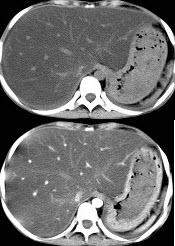

男,57岁,肥胖、糖尿病、血脂升高,CT扫描如下图,请问诊断或描述错误的是哪一项( )

A:肝硬化

B:脂肪肝

C:肝脏增大

D:密度均匀减低

E:血管影清唽可见